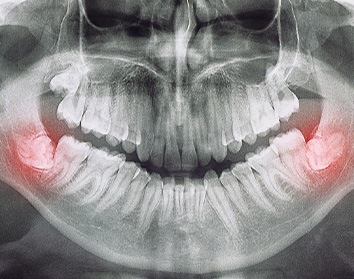

In short, wisdom teeth are the third set of molars. They typically make an appearance in a person’s late teens or early twenties. With that said, there are some patients who don’t develop them at all! That’s why it’s so important for our dentist in Morgan Hill, Dr. Hong, to take new X-rays every year. This ensures that she can monitor what’s going on underneath the gumline and, if necessary, perform an extraction.

Some people go their whole lives without their wisdom teeth causing trouble. In fact, removing them is only necessary if a problem could occur otherwise. For example, the wisdom teeth might:

- Not have sufficient room to erupt past the gumline, becoming impacted (stuck) and causing pain.

- Only emerge partially, making them difficult to clean and increasing the risk of tooth decay and infections.

The extraction process will look a bit different depending on whether or not the tooth in question is trapped underneath the gumline. If that’s the case, then an incision needs to be made in the gums first. Then, the tooth can be removed section by section, and we can tend to the extraction site. Conversely, if the tooth has already broken through the gumline, then we can simply grip it, rock it loose, and remove it.